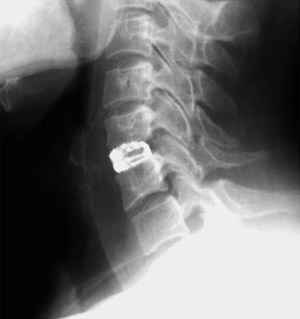

С этого этапа мною используется хирургический микроскоп, позволяющий различать все нервные структуры под увеличением до 16 раз. Это позволяется работать с тканями очень аккуратно, не допуская излишнего травматизма. Вначале удаляется мп диск, а затем и сама грыжа. (Рис.3) Операция заканчивается установкой межтелового импланта - кейджа (протеза диска). Кейдж (в переводе с английского «cage» означает «сетка») представляет собой титановый или пластиковый имплант, заполняемый собственной костной крошкой пациента или другим остеоиндуктивным (костеобразующим) материалом. Кейджи устанавливаются в полость диска, в результате чего восстанавливается высота последнего и соответственно высота фораминального отверстия (через который выходит спинномозговой корешок из позвоночного канала) для исключения сдавления корешка в указанном месте.

Рис. 4. Рентгенорамма шейного отдела позвоночника в боковой проекции. Имплантированный в межтеловое пространство С5-С6 кейдж, заполненный костной крошкой. |